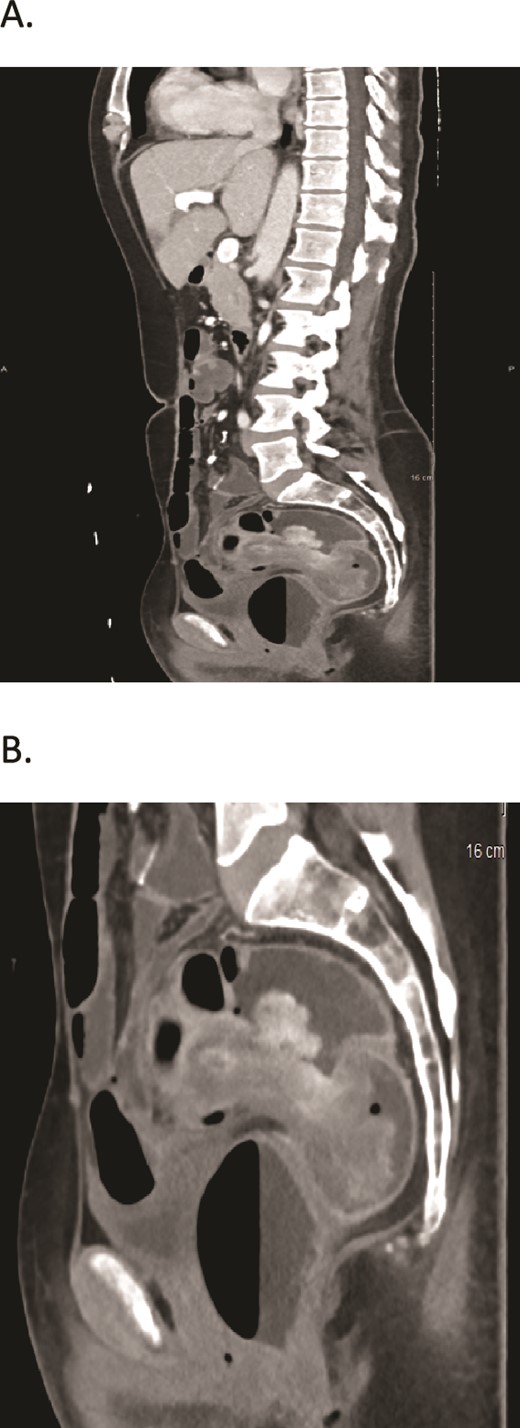

A computed tomography (CT) scan was done and it revealed two large fungating intraluminal sigmoid masses. The largest is 5 × 5.5 × 4.3 (AP, transverse), about 10 cm from the anal verge, and associated with “target sign” in the sigmoido-rectal area suggestive of intussusception with no signs of bowel obstruction or lymph node involvement (Fig. 1).

(A, B) CT scans show two large fungating intraluminal sigmoid masses. The largest is 5 × 5.5 × 4.3 (AP, transverse), about 10 cm from the anal verge, and associated with “target sign” in the sigmoidorectal area.